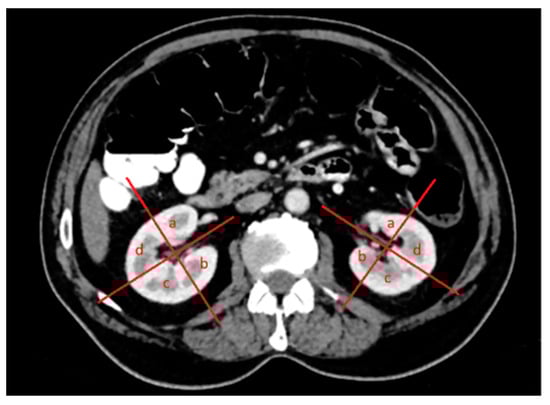

2.1. Percutaneous Microwave Ablation Therapy

2.3. Laparoscopic Ultrasound-Guided Percutaneous Microwave Ablation Therapy